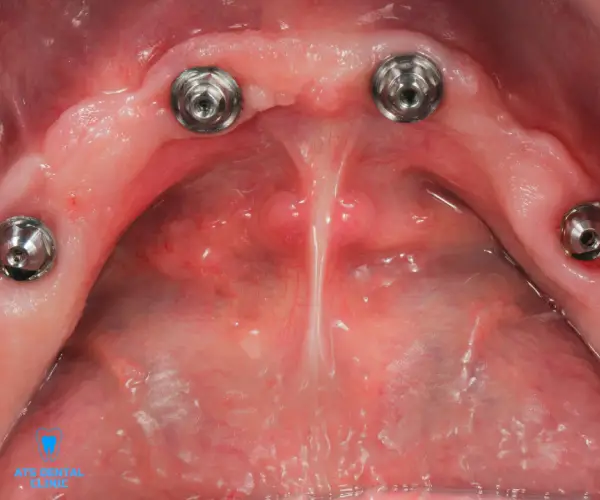

Losing all your natural teeth can significantly affect your ability to eat, speak, and smile confidently. At ATS Dental Clinic, we specialize in creating custom-fitted complete dentures that restore not only your smile but also your facial structure and chewing efficiency as part of Full Mouth Rehabilitation treatment in Thoraipakkam. Our dentures are designed with high-quality, natural-looking materials for comfort, durability, and aesthetics—so you can enjoy life without compromise.